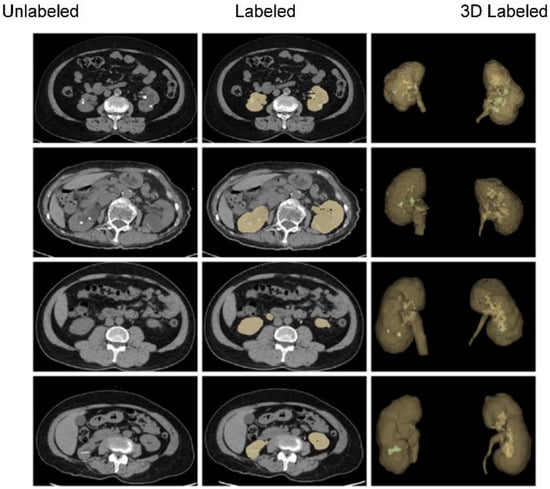

3.1. Data Acquisition and Annotations

3.1.3. Data Annotations